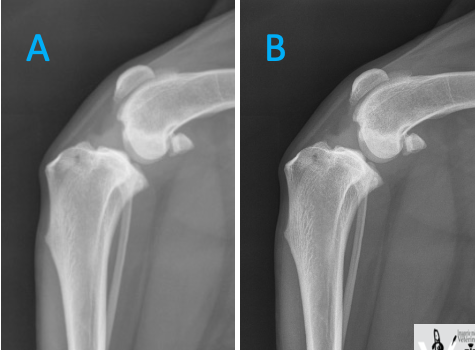

Laquelle des 2 radiographies a été prise avec un filament de taille plus petite?

B : on y voit mieux les rebords osseux. Ici, c’est une partie du corps immobile et on peut se permettre d’augmenter le temps afin de diminuer le mA et donc le filament.

La taille du filament affecte le mA : plus petit = mA plus bas

À mAs équivalent : temps augm, mA diminue => permet d’avoir une meilleure netteté